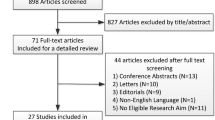

Reports of arterial ischemic stroke due to a cerebral arteriopathy after herpes zoster (shingles) have been described for at least 7 decades in the English-language medical literature (Cope and Jones 1954). Interest in this association has been reignited by ever more convincing evidence that vaccination with the live attenuated zoster vaccine (Zostavax) reduces the likelihood of acute ischemic stroke in the vaccine recipients. For example, a recent retrospective analysis of more than 1.6 million US Medicare beneficiaries who had received Zostavax documented a lower incidence of stroke than found in a control group (Yang et al. 2021). An earlier smaller study analyzed 265,568 adults (50–79 years of age) and concluded that Zostavax reduced the likelihood of stroke by 50% (Klaric et al. 2019). However, a third study that analyzed 87,405 adults (66 years or older) failed to find a protective effect of Zostavax (Yang et al. 2020). The latter study, however, did document a substantial risk of stroke following herpes zoster. In the pediatric literature, varicella-zoster virus (VZV) has also been linked to arteriopathic stroke in childhood (Elkind et al. 2016). A cerebral arteriopathy identified in pediatric stroke patients within 6 months of chickenpox is called “post-varicella arteriopathy.” Because of the importance of this question about whether stroke occurs after herpes zoster and, therefore, whether vaccination against herpes zoster can prevent stroke, we have reviewed the data about neuropathogenesis of stroke that follows varicella-zoster virus (VZV) infection, including primary infection varicella (chickenpox), and the reactivation from latency, herpes zoster (shingles), (Weller 1983).

After carrying out an extensive literature review, we propose in this review that the pathogenesis of arteriopathic stroke after herpes zoster in an adult parallels that of arteriopathic stroke after varicella in children. In both situations, VZV particles present in neuronal ganglia travel via afferent neuronal branches to cerebral arteries, leading to a focal vasculitis and arterial ischemic stroke. This hypothesis is summarized in Fig. 1. To arrive at this conclusion, we include important experimental data about neurological disease caused by a nonhuman herpesvirus closely related to VZV: pseudorabies virus (PRV), a herpesvirus of swine that can also infect humans in close contact with PRV-infected pigs (He et al. 2019).